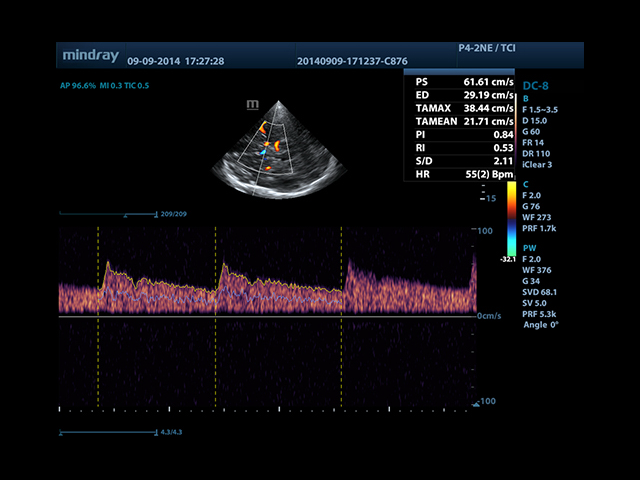

Mindray DC-8 Exp оснащен новым поколением датчиков с увеличенным количеством элементов и инновационной технологией "3T". Это позволяет достичь высокой детализации и качества изображения. Благодаря новейшей технологии iFlow, можно визуализировать даже самые мелкие сосуды и кровеносные пути.

Сверхширокополосная нелинейная обработка изображений снижает визуальные шумы на 30% по сравнению с другими системами. Технология iClear позволяет устранить зернистость изображения, а iBeam (технология пространственного компаундинга) обеспечивает высокое качество сканирования органов и тканей под различными углами.

• Smart Doppler - автоматическая подстройка расположения рамки цветового доплера и контрольного объема импульсно-волнового доплера нажатием кнопки.

• Автоматическая трассировка допплеровского спектра с расчетом параметров и индексов

• Smart Doppler™ - автоматическая подстройка расположения рамки цветового допплера и контрольного объема импульсно-волнового допплера